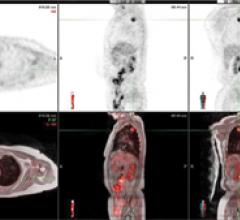

Since it was named “Invention of the Year” by TIME magazine in 2000, positron emission tomography/computed tomography (PET/CT) has been hailed as a winning combination. It captures anatomical information from the CT and functional information from the PET to create a fused image at once, reducing some of the challenges that occur in fusing two images acquired at separate times from separate modalities.

Multimodality imaging in medicine can provide a physician with tools for making an accurate diagnosis prior to making treatment recommendations and helps the physician to lessen the potential for restaging, simplifying the image evaluation process and improving patient care in the future. The benefits also can be applied to the improvement of imaging in clinical trials, where precision and standardization is a necessity. For many diseases, including cancer, heart disease and certain brain disorders, the current and typical imaging process requires the acquisition of both positron emission tomography (PET) and computed tomography (CT) scans.